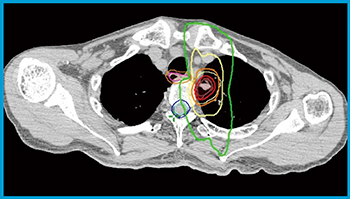

図4 左上葉肺腺癌2

病巣は一部壁側胸膜に浸潤を認め,食道にも近接している。線量分布上,脊髄,食道の線量を抑えられている。食道はたまに移動することがあるため,治療の際には注意が必要である。

食道(○),食道PRV(+3mm)(○),脊髄(○),脊髄PRV(+3mm)(○),GTV(○),PTV(○),等線量曲線は外側より16.7Gy(○),33.3Gy(○),50Gy(=処方線量)(○),66.7Gy(○)